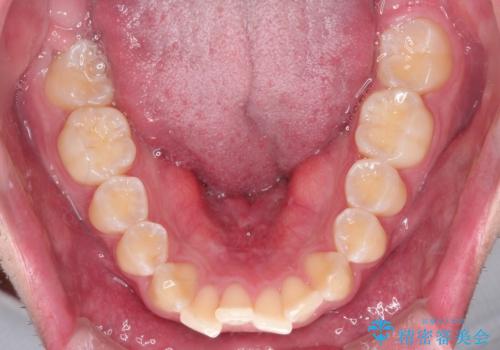

【インビザライン】短期間で出っ歯を治したい

- 出っ歯と口元の突出感が気になるということで来院されました。抜歯矯正も考えられますが、今回は早く終わらせたいという要望があり非抜歯での治療にしました。また遠方から来院されているため、来院回数のおさえられるインビザラインを選択しました。

非抜歯での治療のため、今回はスペース確保のために遠心移動とおもにIPRの処置を取り入れました。